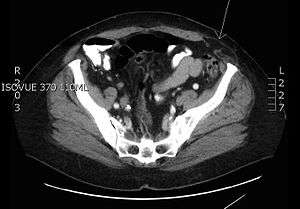

| Transverse CT image of the abdomen in a patient with a Spigelian hernia (arrow). | |

A Spigelian hernia (or lateral ventral hernia) is a hernia through the spigelian fascia, which is the aponeurotic layer between the rectus abdominis muscle medially, and the semilunar line laterally. These are generally interparietal hernias, meaning that they do not lie below the subcutaneous fat but penetrate between the muscles of the abdominal wall; therefore, there is often no notable swelling.

Spigelian hernias are usually small and therefore risk of strangulation is high. Most occur on the right side. (4th–7th decade of life). Compared to other types of hernias they are rare.[1]

Patients typically present with either an intermittent mass, localized pain, or signs of bowel obstruction.[1] Ultrasonography or a CT scan can establish the diagnosis, although CT scan provides the greatest sensitivity and specificity.[2]